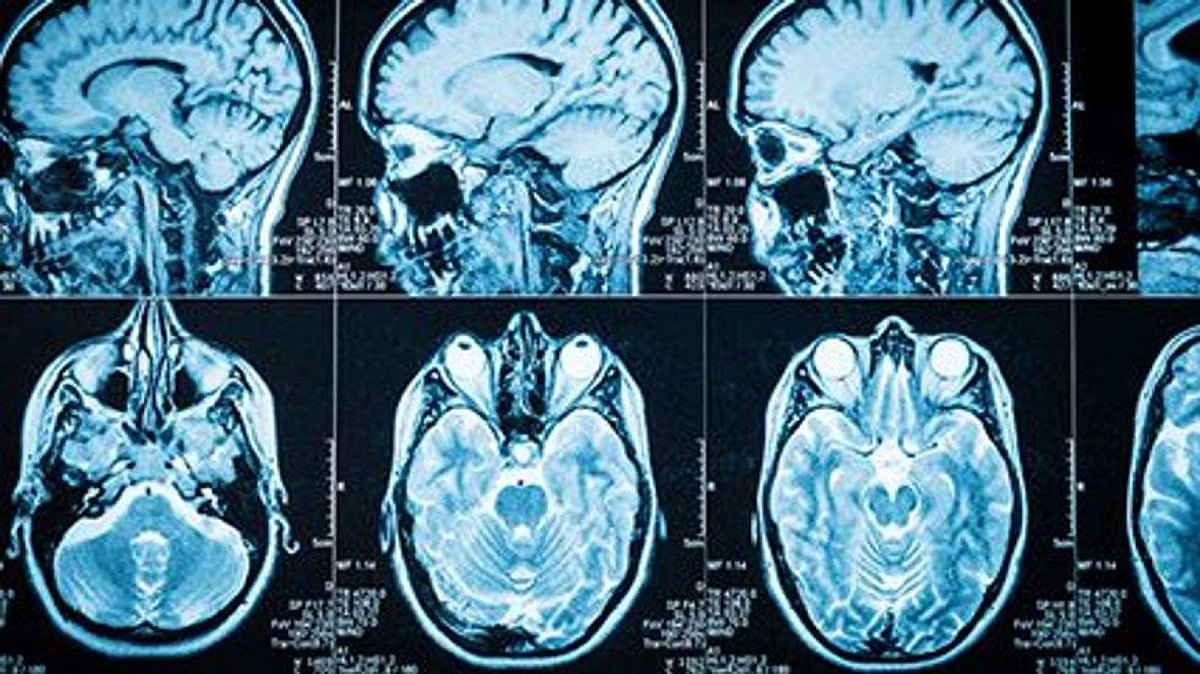

FRIDAY, Jan. 23, 2026 Brain tumors are abnormal growths of cells in or around the brain. They can be primary (originating in the brain) or secondary (metastatic